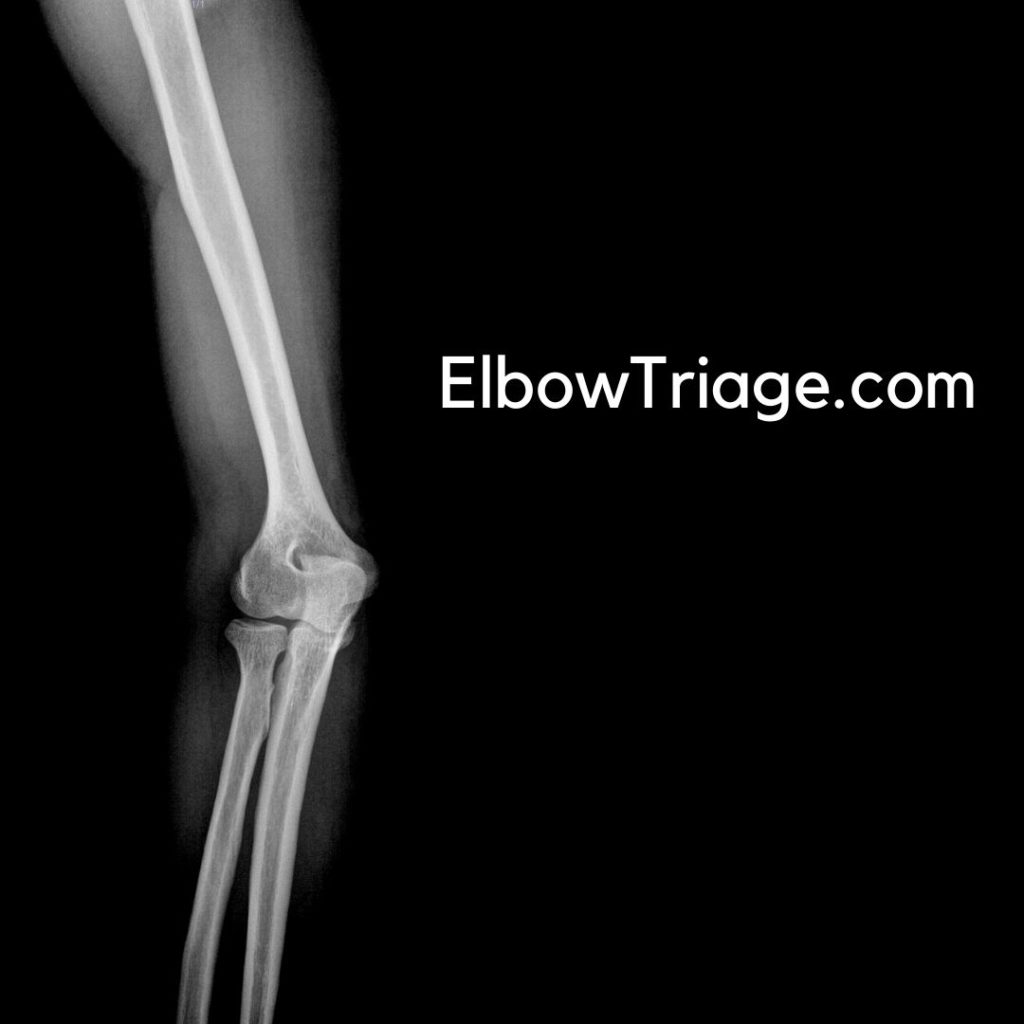

4. Imaging and Diagnostic Modalities

1. X-ray (First-Line Imaging)

- AP and lateral views are essential.

- Oblique views may be required for radial head fractures.

- Fat pad sign (Sail sign) indicates occult fractures.